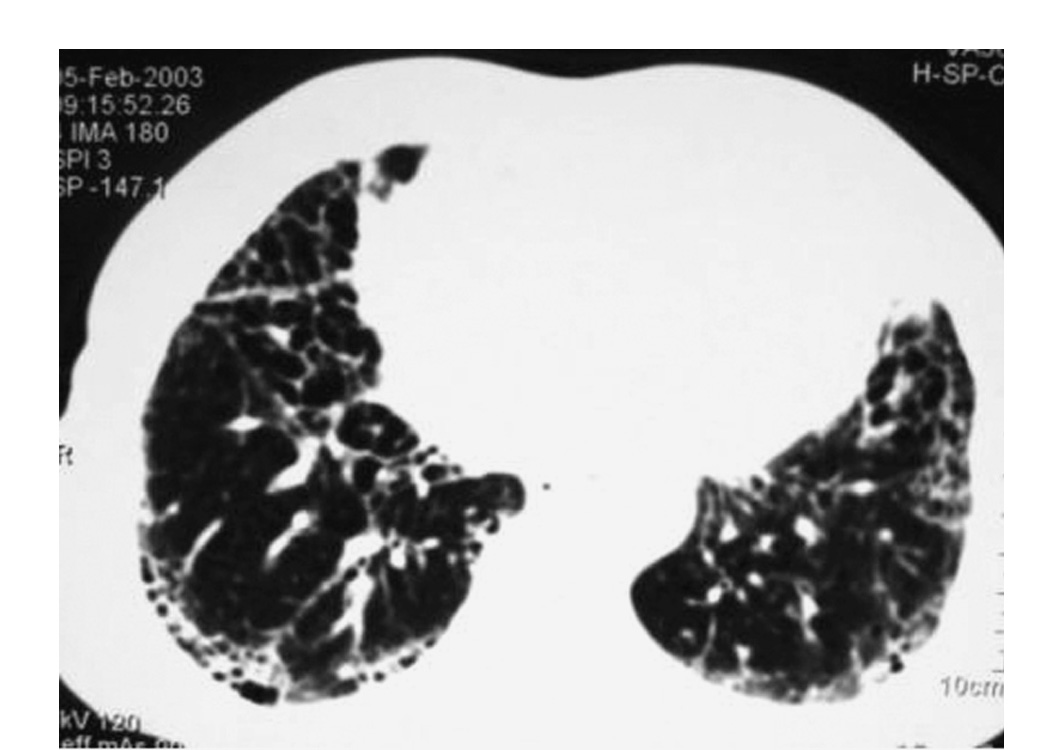

肺纖維化圖片

_特發性肺纖維化的高清CT圖像

_特發性肺纖維化ct表現圖